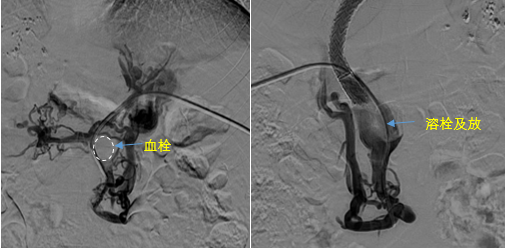

• 血栓攔路,如何破局——罕見(jiàn)巨大門(mén)靜脈血栓TIPS手術(shù)實(shí)錄

血栓攔路,如何破局——罕見(jiàn)巨大門(mén)靜脈血栓TIPS手術(shù)實(shí)錄

日前,西安國(guó)際醫(yī)學(xué)中心醫(yī)院消化病醫(yī)院為一位罕見(jiàn)巨大門(mén)靜脈血栓患者行TIPS手術(shù)。將患者體內(nèi)的“定時(shí)炸彈”拆除。9月份的一天,李女士晚飯后發(fā)覺(jué)惡心,嘔吐出鮮紅色的血塊,隨即又出現(xiàn)了黑便。在醫(yī)院檢查發(fā)現(xiàn)是食管胃底靜脈曲張破裂出血?!?/p>